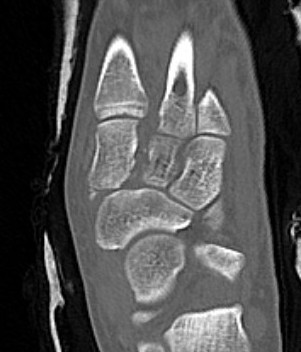

CT

Fleck sign

Fleck sign with inter-cuneiform widening

Dorsal subluxation of the metatarsal